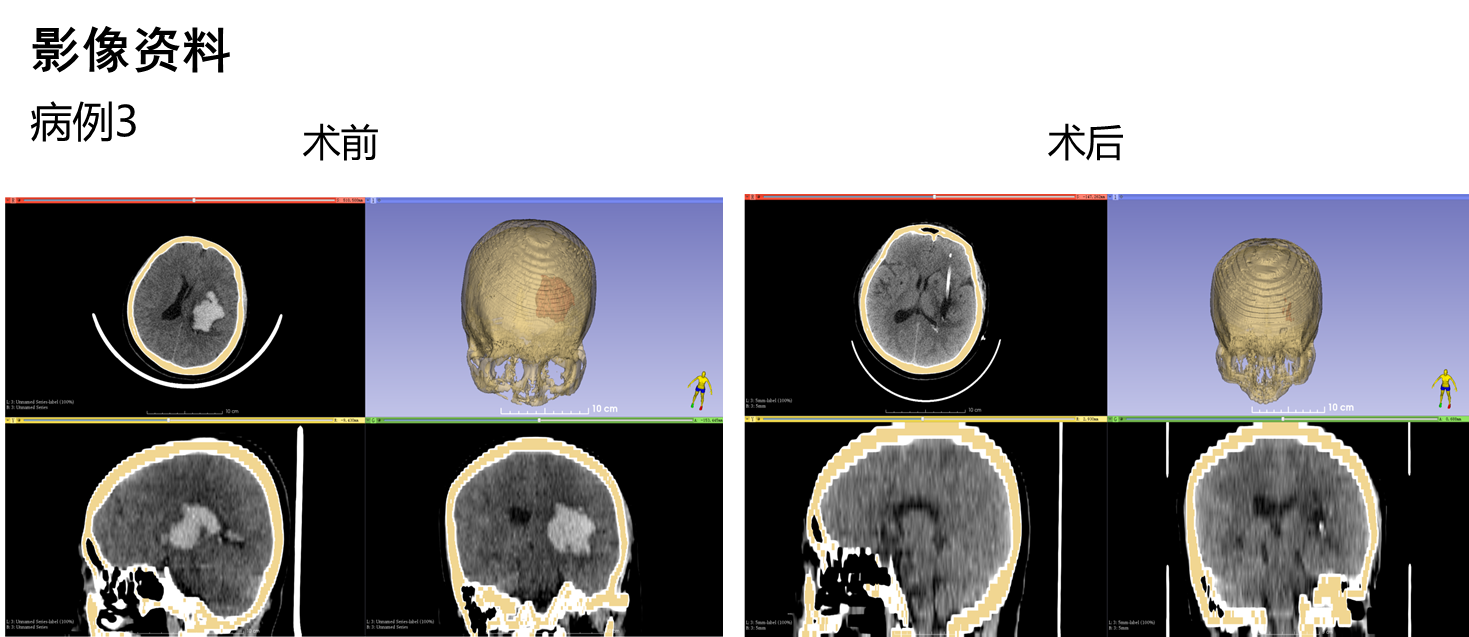

病例术前术后影像:

新型内窥镜技术可实现血肿清除手术全程可视化,包括血肿穿刺、血肿清除及血肿腔内精准电凝止血,手术切口长2.5cm,仅需单一直径1cm骨孔,镜体工作通道外径小于7mm,手术在全内镜内操作,十分微创,血肿部位的深浅在新内镜手术中无难度差别,新型内窥镜血中可视能力,不但可以在全程清晰可视下一次性清除绝大部分血肿,而且还可在有明显出血的血肿腔内轻易找到出血点并进行精准电凝止血,基于新型内窥镜所具有的颠覆性功能,有理由预判脑出血治疗的一些尚没有结论的重要问题的结果。